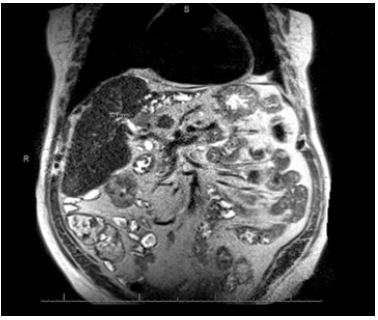

The gastroenterology service was consulted on hospital day 3 for evaluation of cirrhosis and new-onset obstructive jaundice. By this time, the patient’s abdominal pain had resolved, and his conjugated bilirubin had fallen to 2.3 mg/dL, indicating a possible passed stone. Magnetic Resonance Cholangiopancreatography (MRCP) was ordered for further workup of the liver mass and revealed an ill-defined, hypoenhancing mass at the liver hilum, with isolated left intrahepatic biliary dilatation and lobar atrophy (Figure 1).

Figure 1: Hypoenhancing mass measuring 32.7 mm at the liver hilum.